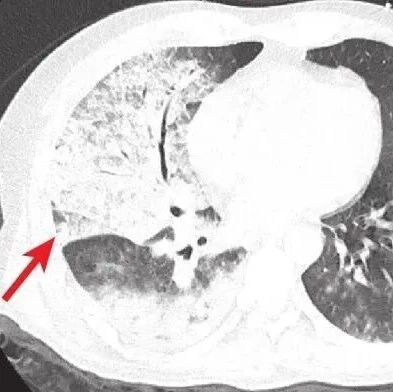

NEJM麻省总医院病例:双肺十余个空洞性结节及肿块,咳嗽发热、右眼一夜失明……致命感染因何迅速经血行...